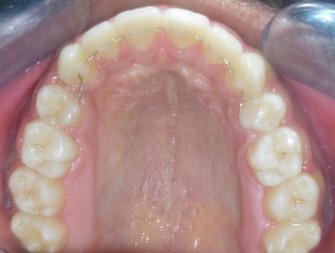

The soft tissue frontal and profile improved dramatically. (Figure 7a-b). The bilateral posterior crossbite was corrected. The severe increase in overjet of about 13mm was effectively reduced to 3mm and the severe deep bite was also corrected (Figure 7c,Figure 7d). Fixed maxillary and mandibular lingual retainers were given. (Figure 7e, Figure 7f). Post orthodontic treatment, normal root inclinations of the teeth and normal alveolar bone levels was observed. (Figure 8).

Figure 7e.Post-treatment intra-oral-Upper occlusal

Figure 7f.Post-treatment intra oral-Lower occlusal

Post treatment lateral cephalometric radiograph was taken to assess the treatment changes. (Figure 9). The changes in maxilla in the anteroposterior direction was insignificant, however an increase in the length of the mandible measured from Condylion (Co) to Gnathion (Gn) and an increase in anterior facial height was observed. Maxillary incisors were retracted dramatically by 8mm and the mandibular incisors were proclined by 3mm to camouflage the skeletal class II malocclusion.(Table 1). Effective expansion of the maxillary constriction as an end-of treatment goal was achieved. (Figure 10a,Figure 10b).